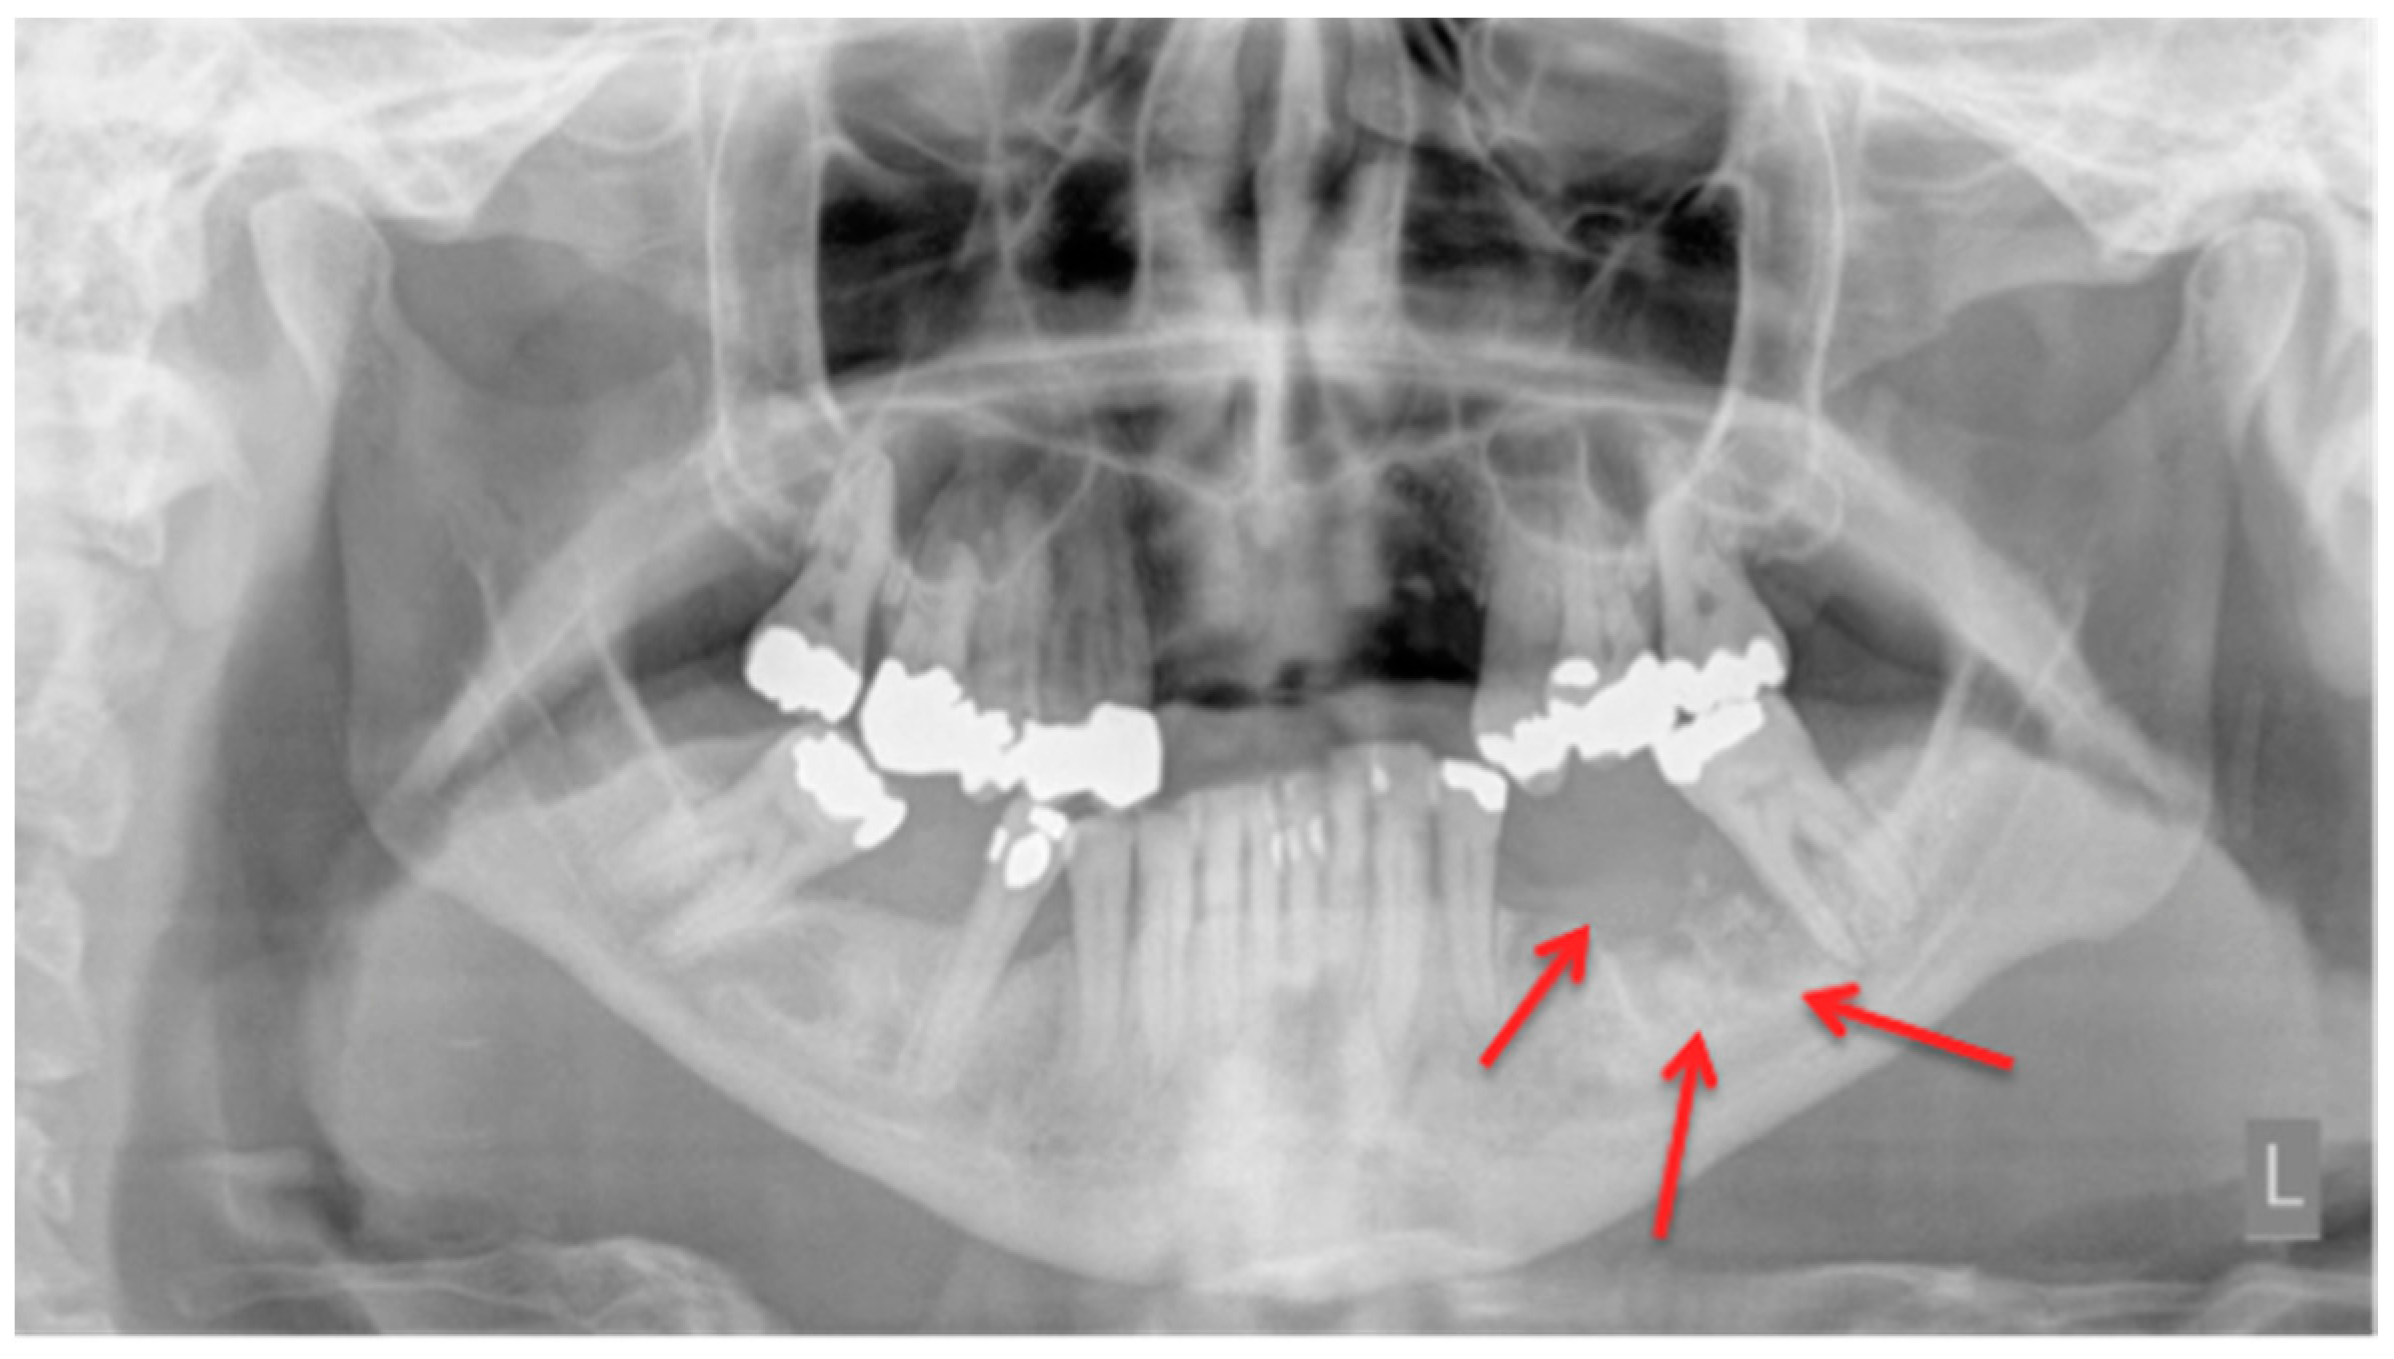

In a daily routine, a clinical examination and a radiograph are the minimum examinations required in order to detect lesions and to provide data for a follow-up appointment. For Marx et al., panoramic imaging is the image of choice for a routine dental assessment in these patients [13]. Figure 1, Figure 2 and Figure 3 exemplarily depict typical findings of panoramic radiographs.

Figure 1.

Panoramic radiograph: Patient: 48 years old, female, metastatic breast cancer, zoledronic acid. Red arrows point to the necrotic area. The corresponding magnetic resonance imaging (MRI) images are shown in Figure 6 and Figure 7. American Association of Oral and Maxillofacial Surgeons (AAMOS) staging: stage 2.